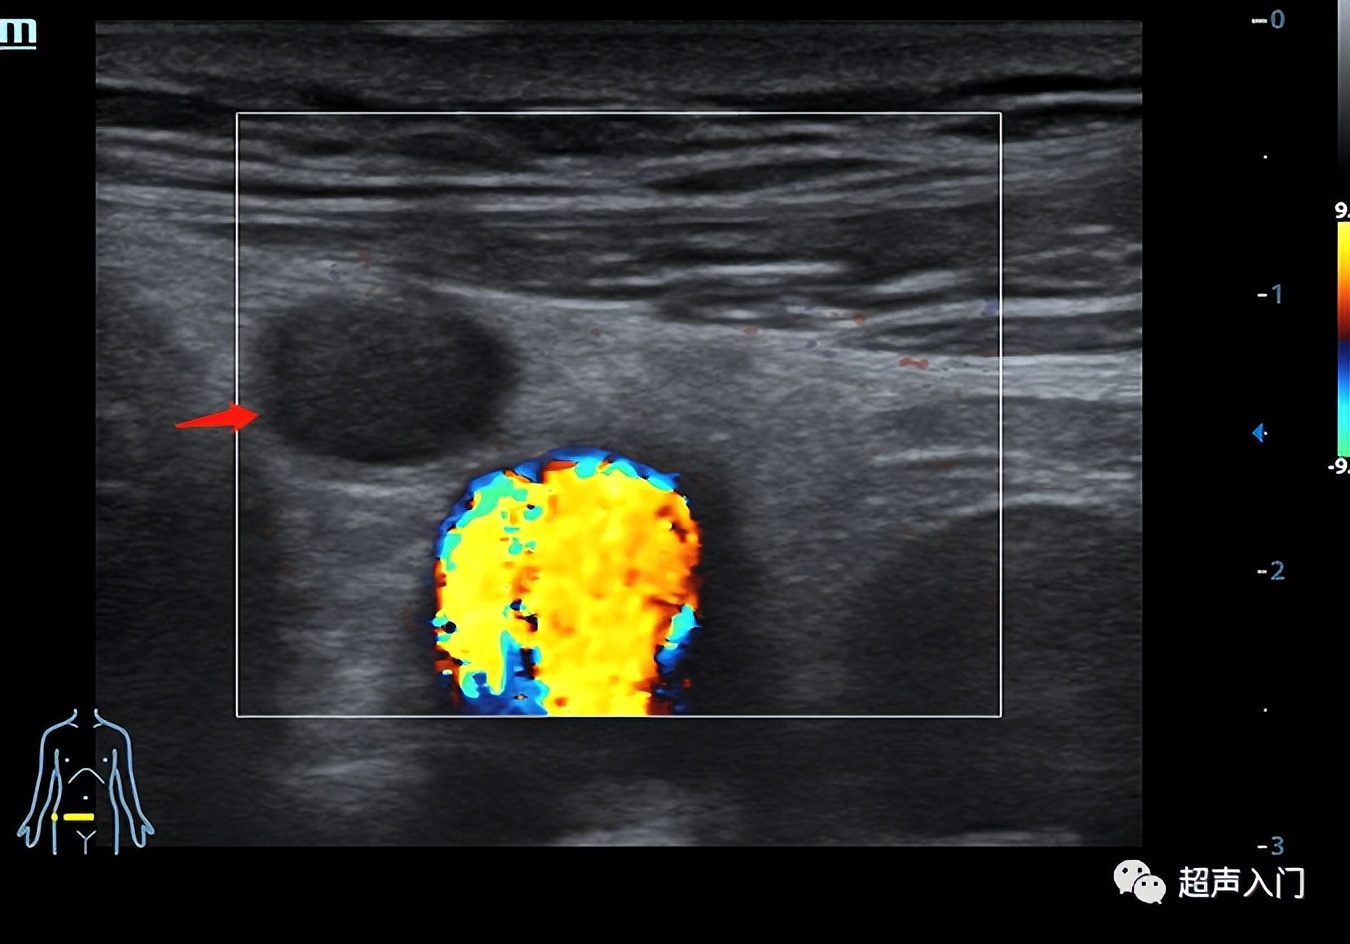

下图就是例子:

1、多切面

如果发现异常回声,至少两个切面都扫及了,才能确定有异常回声,如果一个切面扫及异常回声,有可能是异常的,也有可能就是个伪像,换个切面也许就一目了然。